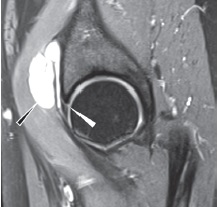

Как уже было сказано ранее, повреждение суставной губы чаще всего локализуется в передне-верхнем квадранте, что связано с наибольшей функциональной нагрузкой на этот отдел и повторяющейся травматизацией вследствие ФАИ. Нормальная суставная губа вертлужной впадины выглядит как треугольник слабого МР-сигнала с гладкими краями, плавно переходящий в хрящ вертлужной впадины или отделенный от него сублабральной бороздой. Распространенной ошибкой при оценке МРТ является определение сублабральных углублений как повреждений. Это нормальные варианты, которые, как правило, не распространяются на всю толщину суставной губы, доходят проекционно до уровня субхондральной кости и чаще наблюдаются в передне-нижней или задне-нижней части вертлужной впадины [78]. Расположение сублабральной борозды в передне-верхнем отделе стоит внимательно дифференцировать с повреждениями, которые встречаются в этой области чаще [79] (рис. 7).

Рис. 7. Сублабральная борозда:

а — МРТ-картина сублабральной борозды;

b — вид сублабральной борозды во время артроскопии

Fig. 7. Sublabral sulcus:

а — MRI picture of sublabral sulcus;

b — sublabral sulcus arthroscopy view

Чаще всего встречаются продольные повреждения хондро-лабрального перехода с отслойкой или без отслойки суставного хряща от подлежащей субхондральной кости или горизонтальное расслоение суставной губы, нередко ведущее к образованию интралабральных или паралабральных кист, в том числе и в зоне прилегания сухожилия подвздошно-поясничной мышцы с распространением кисты по ходу сухожилия [80, 81].